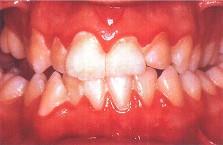

下列哪项不是慢性龈缘炎的临床表现 ( )

A牙龈充血肿胀

B探诊龈沟出血

C龈沟深度超过3mm

D牙周附着丧失

E无牙槽骨吸收